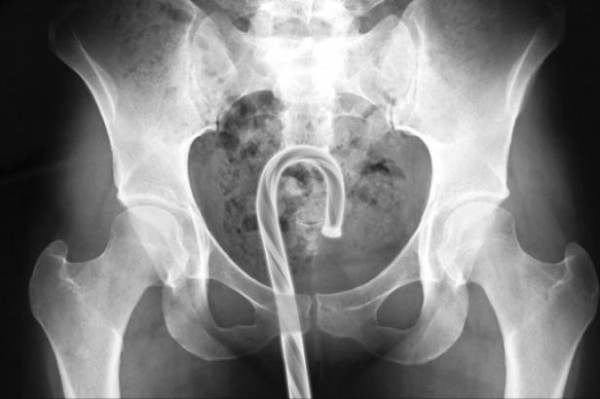

3- Les objets coincés dans...enfin vous voyez quoi !

Ouais c'est pas glorieux mais...toutes ces histoires de pompiers et d'infirmiers que vous entendez ne sont pas des légendes ! Il y a bien des gens qui arrivent aux urgences en disant qu'ils ont glissé sur une bouteille de bière qui s'est malencontreusement logée par erreur sans faire exprès sans le vouloir de façon inopinée dans leur rectum.... Mais oui mais oui allez on ne dira rien mettez vous sur le ventre !

Voila ce que c'est que de faire l'amour avec un aveugle !